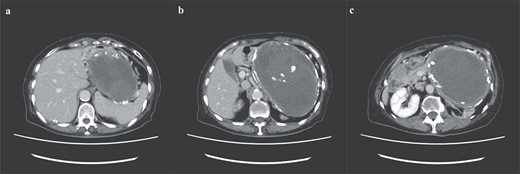

A 74-year-old Asian woman had been treated for diabetes mellitus but had stopped treatment on her own. The HbA1c level increased sharply to 16%. Blood samples showed no abnormal findings such as elevated levels of tumor markers (Table 1). There was no history of abdominal imaging, sudden abdominal pain, abdominal trauma, or abdominal surgery. Contrast-enhanced abdominal computed tomography (CT) revealed a large hematoma-like cystic lesion in the pancreatic tail (Fig. 1a–c). Calcification of the wall and internal septum was prominent. Magnetic resonance imaging (MRI) demonstrated a 156 × 112 mm marginal T1W high signal (Fig. 2a) and an internal T2W uneven low signal (Fig. 2b) on the dorsal side of the stomach, suggesting a hematoma-like cystic lesion. Diffusion showed a high signal intensity, but abnormal enhancement was not observed (Fig. 2c). Considering the possibility of intra-abdominal dissemination of the cystic tumor via a puncture, the patient underwent distal pancreatectomy and splenectomy with lymph node dissection for diagnostic and therapeutic purposes. The cyst wall adhered strongly to the surrounding tissue (Fig. 3); however, no adverse events were noted during the operation. The operating time was 7 h 19 min, and blood loss was 809 ml. The patient was discharged 11 days postoperatively, with a good postoperative course.

Preoperative abdominal enhanced CT showing a large hematoma-like cystic lesion in the pancreatic tail.